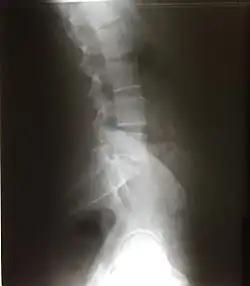

Scalloping vertebrae is the increase in the concavity of the posterior vertebral body. It can be seen on lateral X-ray and sagittal views of CT and MRI scans. Its concavity is due to the increased pressure exerting on the vertebrae due to a mass. Internal spinal mass such as spinal astrocytoma, ependymoma, schwannoma, neurofibroma, and achondroplasia causes vertebrae scalloping.[20]

Curvature

Excessive or abnormal spinal curvature is classed as a spinal disease or dorsopathy and includes the following abnormal curvatures:

- Kyphosis is an exaggerated kyphotic (convex) curvature of the thoracic region in the sagittal plane, also called hyperkyphosis. This produces the so-called "humpback" or "dowager's hump", a condition commonly resulting from osteoporosis.

- Lordosis is an exaggerated lordotic (concave) curvature of the lumbar region in the sagittal plane, is known as lumbar hyperlordosis and also as "swayback". Temporary lordosis is common during pregnancy.

- Scoliosis, lateral curvature, is the most common abnormal curvature, occurring in 0.5% of the population. It is more common among females and may result from unequal growth of the two sides of one or more vertebrae,[21][22] so that they do not fuse properly. It can also be caused by pulmonary atelectasis (partial or complete deflation of one or more lobes of the lungs) as observed in asthma or pneumothorax.

- Kyphoscoliosis, a combination of kyphosis and scoliosis.